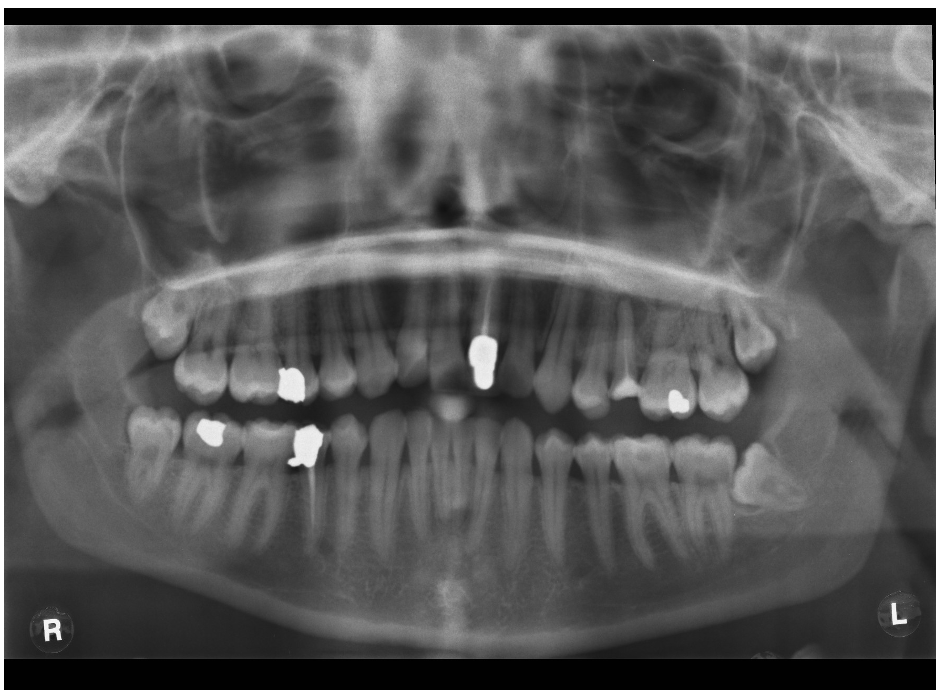

What type of impaction are these third molar?

Disto angular